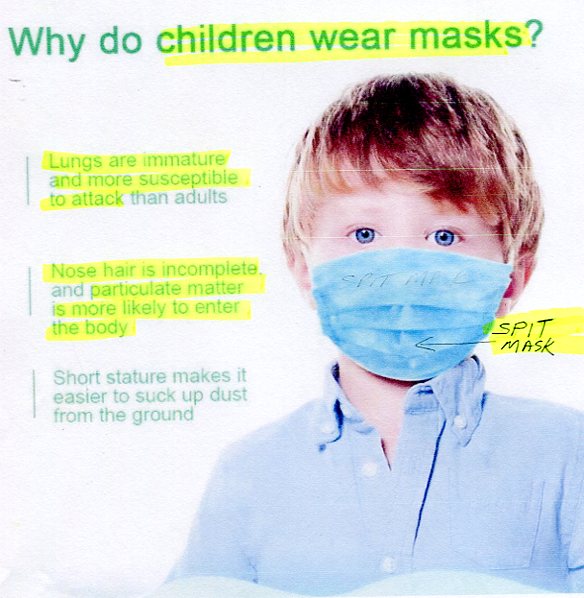

SELF-SUFFOCATING SPIT-MASKS TORTURE

SELF-SUFFOCATING SPIT-MASKS TORTURE

(oxygen-deficient germ-generating atmosphere)

Masks are bacteria traps on kid's breathing orifices

(gov't mandated masks is cruel form of child abuse)

Global, June 2021

watch DOCTORS SPEAK OUT TO PROTECT KIDS

(masks-isolation-tests-sanitizers-vaccines cause harm)